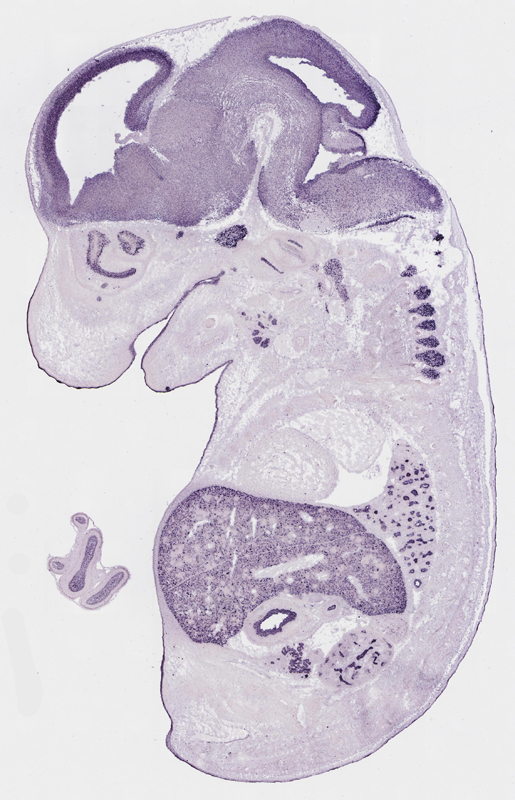

Specimen

euxassay_003287_03:

embryonic day 14.5